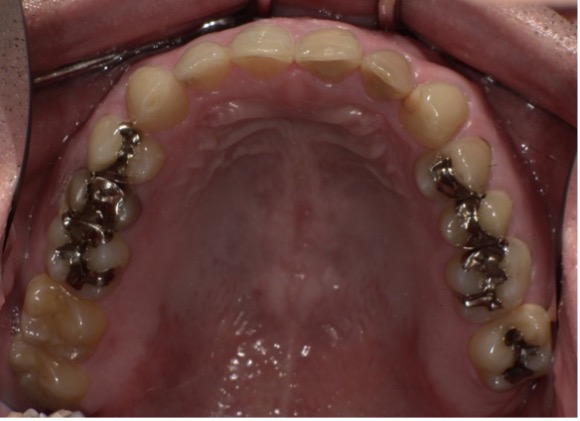

【Before】